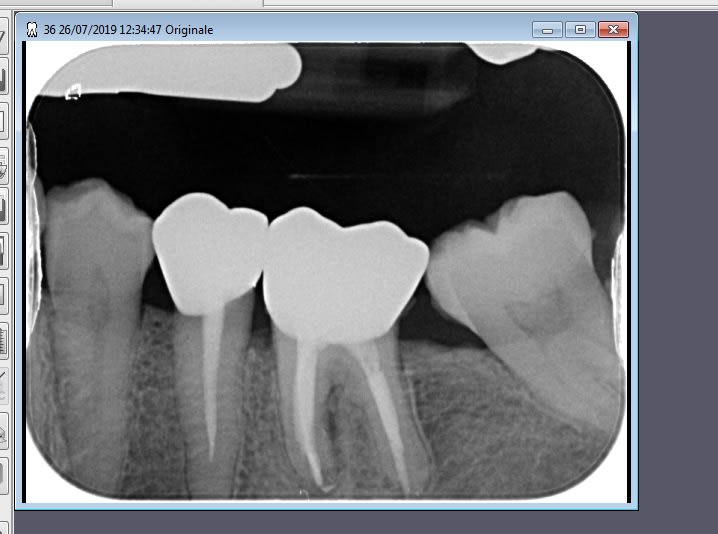

C'est mieux au gutt condensor... tiens une résorption interne! Oui ça tu le fais pas au cône + pâte.

Resor2 y3ab4s - Eugenol